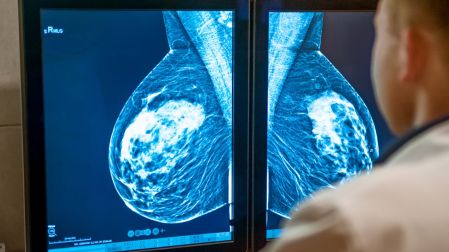

Te puede interesar: Cáncer de mama: 75 % de los casos en México se detectan en etapas avanzadas

- cáncer de mama antes de los 40–50 años

- Mastografía e IRM anual desde edades tempranas en riesgo BRCA